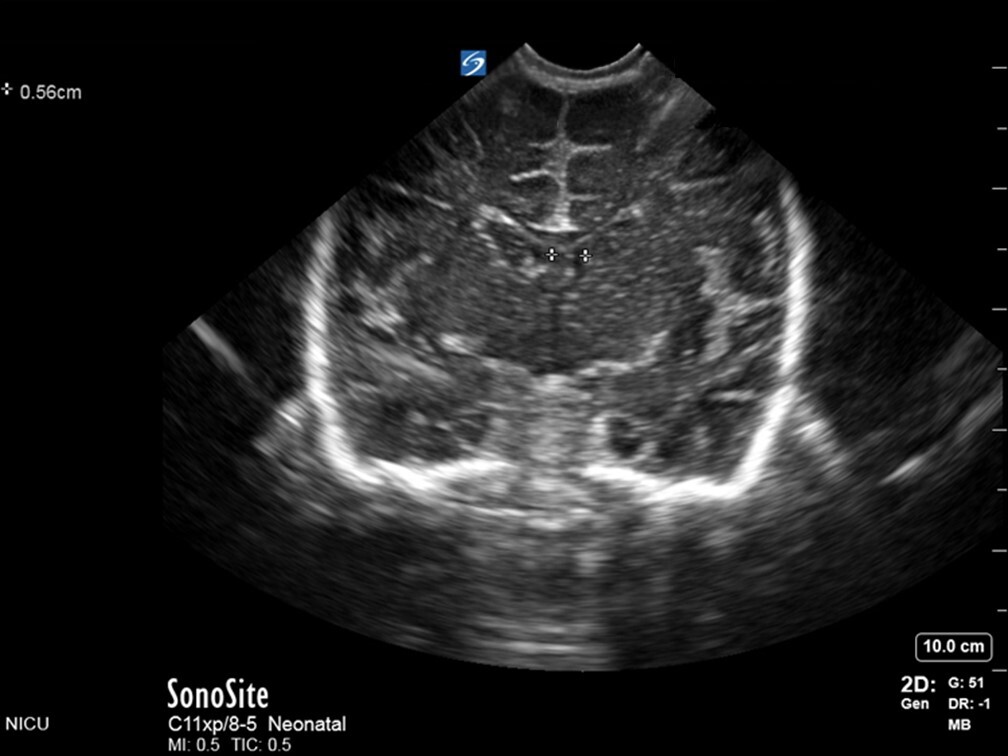

Neonatology Levene Method VI Image